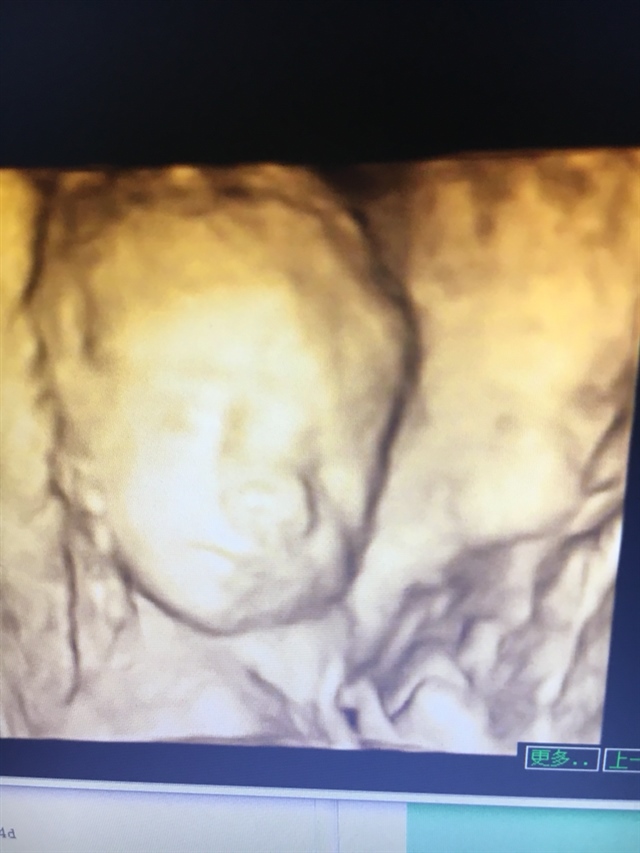

孕16周+5天

好孕